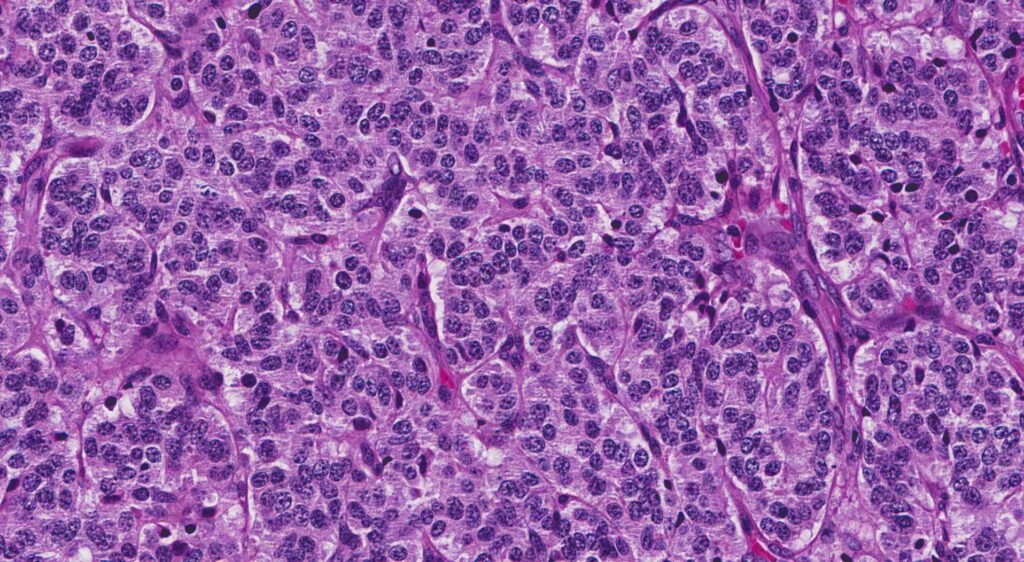

Histológicamente, los tumores carcinoides presentan una arquitectura sólida y trabecular, con células que tienen un citoplasma escaso y núcleos redondeados. Estas células suelen mostrar una citología regular, con escaso pleomorfismo nuclear y mitosis infrecuentes. La presencia de gránulos neuroendocrinos en el citoplasma, que se evidencian mediante técnicas de tinción específicas como la inmunohistoquímica para cromogranina A y sinaptofisina, es característica de estos tumores.

Los tumores carcinoides típicos son considerados de bajo grado. Estos tumores tienen un crecimiento lento y una tendencia a tener un curso clínico menos agresivo. Histológicamente, el carcinoide típico se distingue por sus células uniformes con núcleos redondeados, escaso pleomorfismo y una baja tasa de mitosis. La arquitectura de estos tumores suele ser sólida o trabecular, y las células tumorales muestran una tinción positiva para marcadores neuroendocrinos como la cromogranina A y la sinaptofisina. El pronóstico para los pacientes con carcinoide típico es generalmente favorable, con una alta tasa de supervivencia a largo plazo, dado su crecimiento lento y bajo potencial de metastatización.

Por otro lado, los tumores carcinoides atípicos son considerados de grado intermedio y tienen un comportamiento clínico más agresivo en comparación con los carcinoides típicos. Histológicamente, estos tumores se caracterizan por un mayor pleomorfismo celular, una mayor tasa de mitosis y una mayor necrosis. La presencia de estas características indica una tendencia a un crecimiento más rápido y un mayor potencial para la diseminación metastásica. Aunque todavía se consideran menos agresivos en comparación con otros tumores neuroendocrinos de alto grado, como el cáncer de pulmón de células pequeñas, los carcinoides atípicos requieren un enfoque más riguroso en su manejo debido a su potencial de agresividad aumentado.